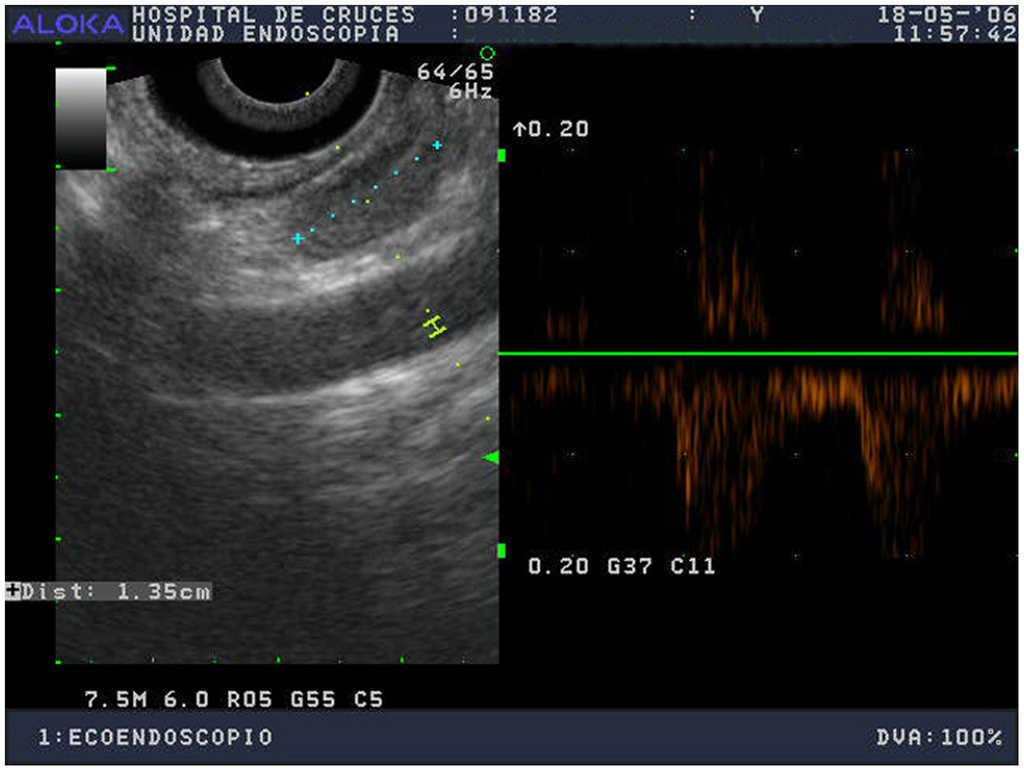

Caso 4La paciente había sufrido una hemitiroidectomía derecha por bocio 7 años antes; la gammagrafía paratiroidea con 99Tc-sestamibi era negativa y la ecoendoscopia objetivó una lesión compatible en posición retroesofágica derecha (fig. 2) y otra más pequeña superior izquierda. La cirugía confirmó un adenoma retroesofágico derecho de 410 mg, correspondiendo la imagen superior izquierda a una paratiroides aparentemente de mayor volumen que lo habitual pero sin aspecto de adenoma. Guiados por la PTH intraoperatoria, extirpamos una única glándula y la paciente 2 años después se mantiene normocalcémica.

Figura 2. Ecoendoscopio sectorial; nódulo hipoecoico y bien definido de 1,35 cm, localizado entre el esófago y la carótida. Se aprecia un discreto halo hipoecoico.